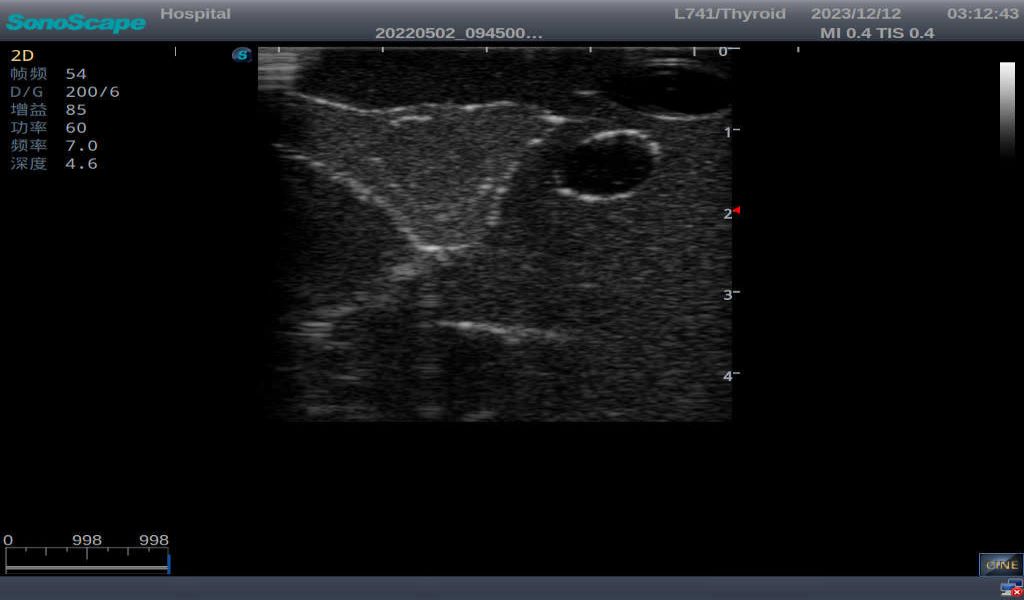

3)       It comes with four (4) thyroid modules and can show five (5) ultrasonic images: normal thyroid, thyroid adenoma, thyroid cancer, nodular goiter, thyroid cyst

Normal thyroid with homogeneous parenchymal echo and well-defined capsule

Thyroid adenoma with well-defined border and smooth uniform halo

Thyroid cancer with irregular mass, unclear border, uneven internal echo or calcification strong echoes

Nodular goiter with irregular border and varying sizes of low echo, isoechoic, or high echo nodules

Thyroid cyst, which fluid area, dark and echo-free area can be seen